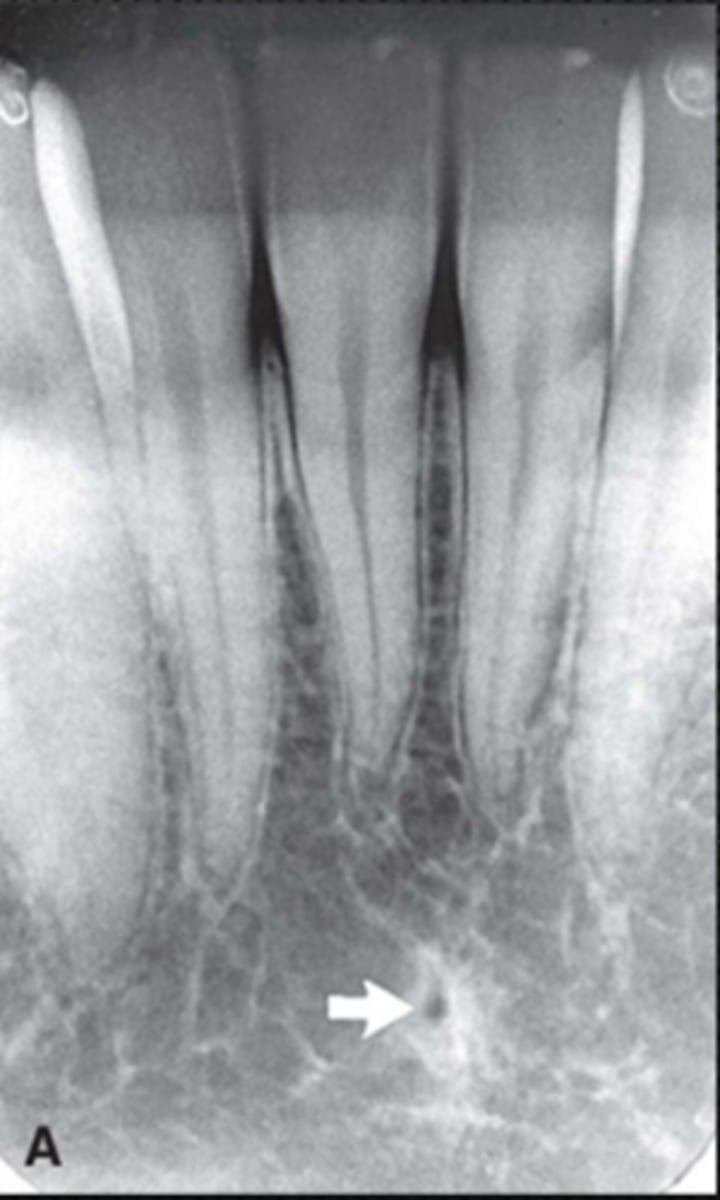

57

New cards

Mandibular canal

What is causing the thick radiolucent line surrounding the dotted line?

<p>What is causing the thick radiolucent line surrounding the dotted line?</p>

Nasopalatine duct

What is the wide, vertical structure indicated by the arrows?

<p>What is the wide, vertical structure indicated by the arrows?</p>